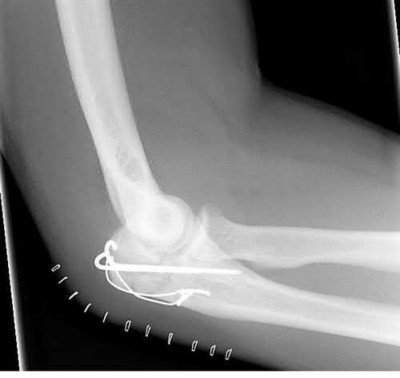

Figures A-C are the radiographs of a 26-year-old male who presents to the emergency department following a motocross accident. Two attempts at a closed reduction by the on-call orthopedic resident were unsuccessful. Figures D and E are the pre-operative axial CT-images that were obtained. The patient undergoes surgical fixation seen in Figure F. Limitations in post-operative dorsiflexion is likely influenced by which of the following?

The rare Bosworth fracture-dislocation is a posterior dislocation of the fibula which becomes entrapped behind the tibia. As demonstrated in this vignette, these injuries are extremely difficult to close reduce secondary to the ridge of the posterolateral distal tibia. The irreducible nature of this injury is a known risk factor for the development of compartment syndrome. The CT images further demonstrate fracture extension to the posteromedial rim (“posterior pilon variant”). In this situation, the only effective method to reduce the fracture is through an open posterolateral approach with the interval between the flexor hallucis longus and the peroneal tendons. This is the same approach that is utilized for fixation of the posterolateral fragment and fibula. Loss of dorsiflexion has been demonstrated following this fracture pattern with posterior fixation. The positioning of the plates in Figure F suggests the

utilization of a posterolateral approach.

Figures A-C: The initial radiographs reveal the posterior subluxation of the talus with associated posterior subluxation of the fibula without significant coronal plane deformity. This deformity should raise the suspicion of a Bosworth fracture-dislocation, especially if closed reduction is not successful. Figures D and E: Axial CT images demonstrating Bosworth fracture-dislocation of the fibula entrapped behind the tibia. Also, note the fracture extension to the posteromedial rim in this posterior pilon variant.

Figure F: Positioning of the plate suggests a posterolateral approach to address both the fibula and posterior malleolus fractures.